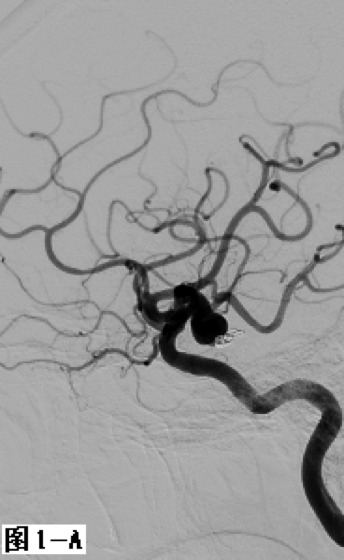

图1 采用经典式双微导管技术栓塞右侧后交通不规则形态动脉瘤。A.DSA显示右侧后交通动脉“葫芦形”不规则动脉瘤;B.在合适的工作角度下降2根微导管置入瘤体内不同位置;C.通过2根微导管交替填塞微弹簧圈,至填塞致密。